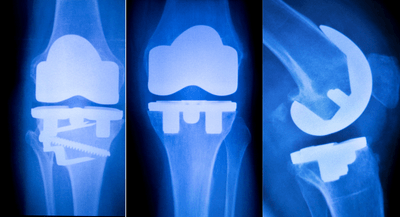

世界の整形外科用インプラント市場は、アプリケーションタイプ別に、脊椎整形外科用インプラント、股関節整形外科用インプラント、膝整形外科用インプラント、頭蓋顎顔面整形外科用インプラント、歯科用整形外科用インプラント、S.E.T(Sports Medicine, Extremities, Trauma)整形外科用インプラントに分類されています。